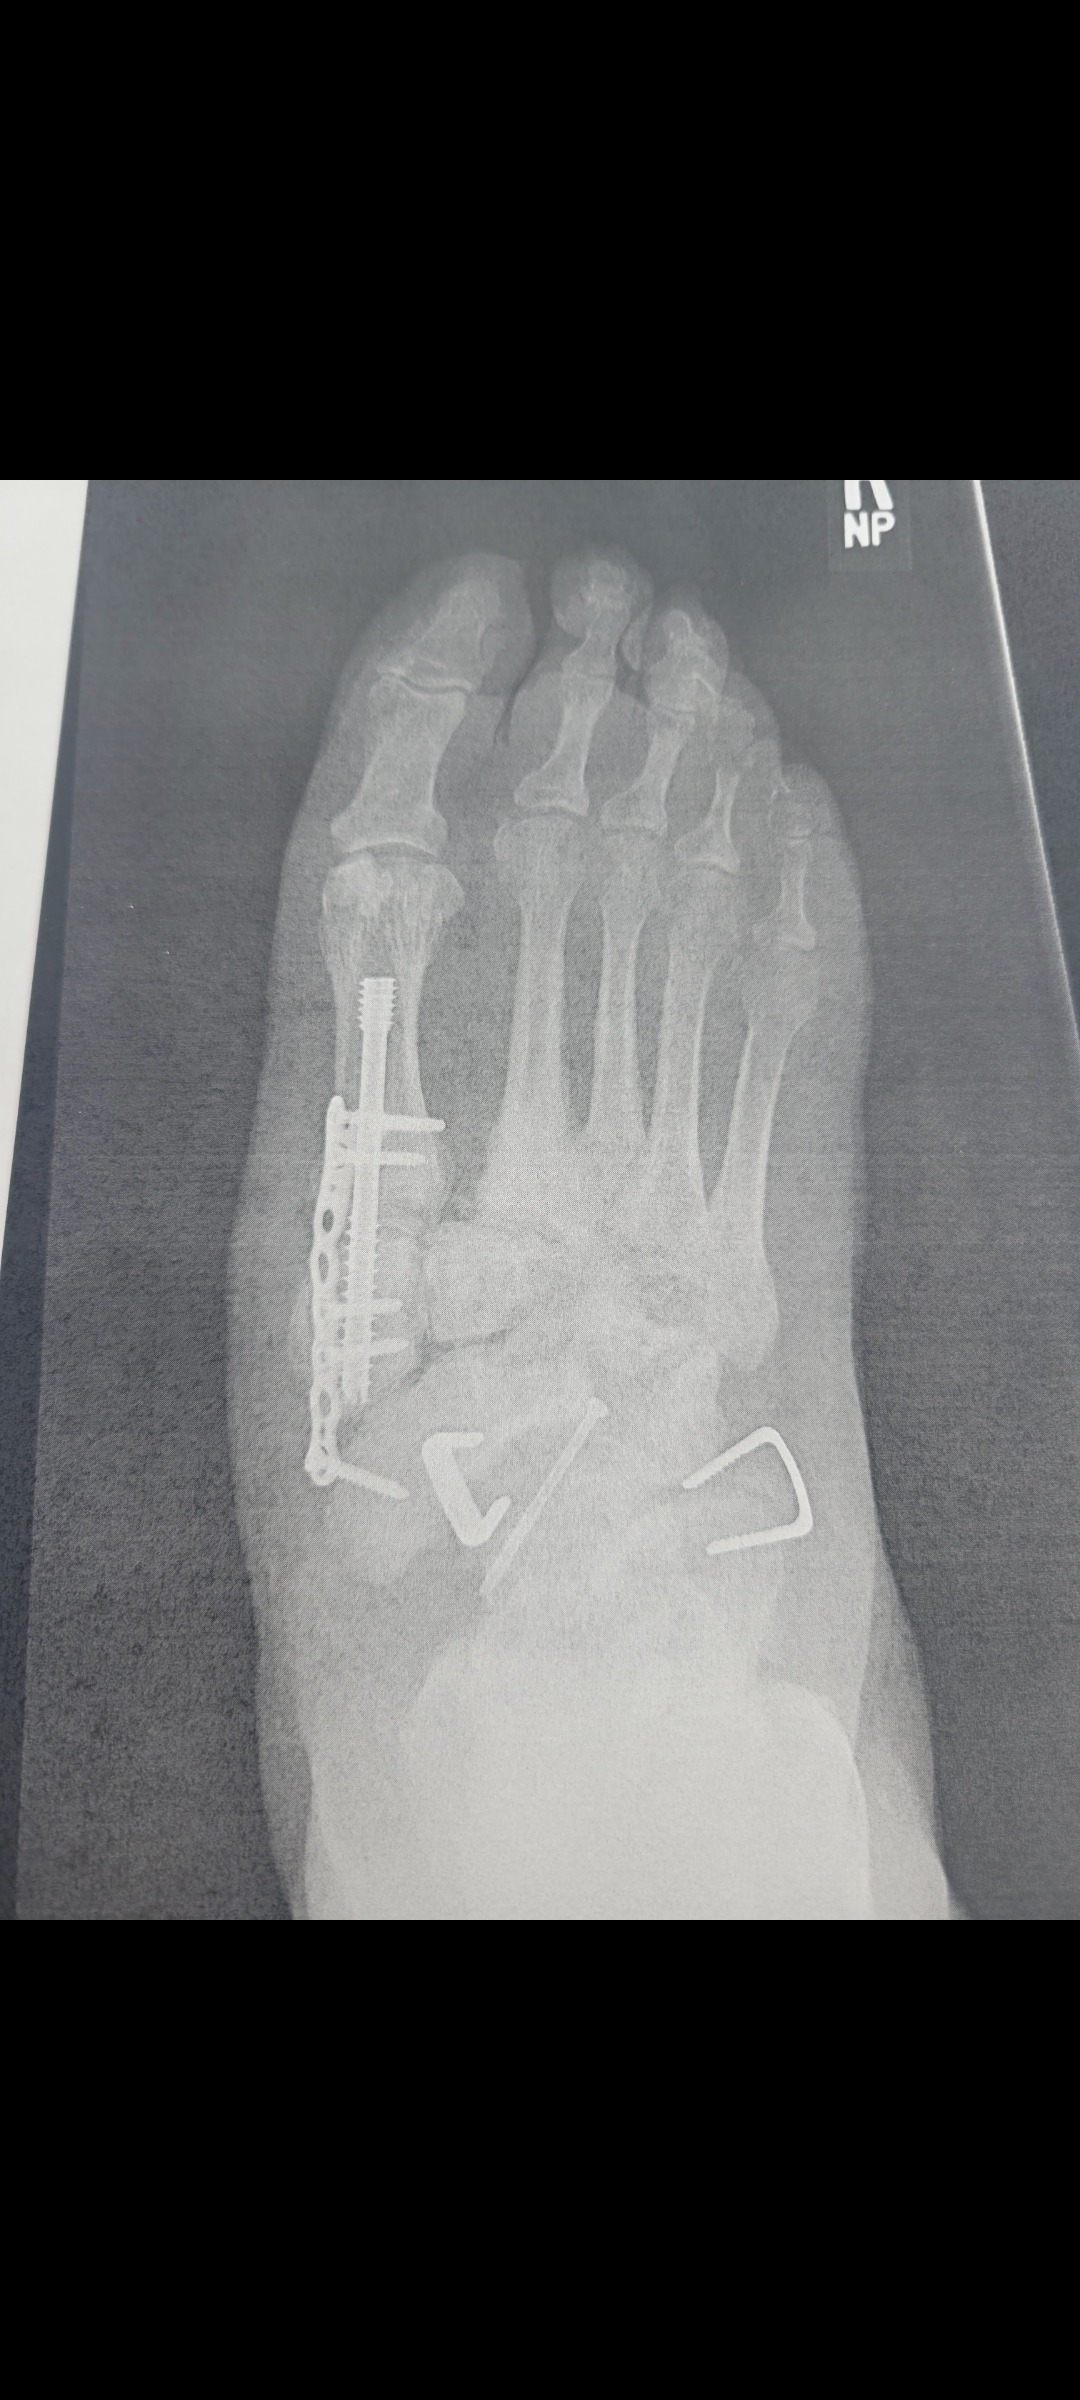

Hi, I am Matthew Olson. Back in November 2024, I was diagnosed with a bone disorder called Charcot foot. It is the deterioration of your bones and joints. At the end of January 2026, I had to have reconstruction surgery on my right foot, which was an extensive surgery. Along with my diabetes and heart complications and the ongoing Charcot foot, just in the past week at my regular doctor's appointment, I found out now I need to have surgery x2 to replace both knees. I have also received confirmation from my doctors that I will not be able to return to work because of my conditions. I've been working on the long road and process to get SS Disability with no income, needing a little help with co-pays, medications, bills, and the everyday cost of living. I would really appreciate what can be donated. Thank you in advance.